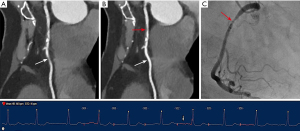

Similarly, the use of MCR significantly improved subjective image quality and interpretability in both subgroups, with a more evident difference observed in the high HR and/or arrythmias group. In the low HR group, although subjective image quality scores performed with MCR displayed a consistent superiority, no significant difference was noted in terms of interpretability by every coronary artery (all P>0.05). Conversely, in the high HR and/or arrythmias group, the application of MCR resulted in a remarkable improvement in interpretability at all levels. Concerning the major three coronary arteries, the greatest benefit in interpretability improvement was found for RCA, where the proportion of arteries considered non-interpretable decreased dramatically from 70.3% to 8.1% (P<0.001). Figures 3-6 display four representative clinical cases, among which Figure 6 contains invasive coronary angiography image.